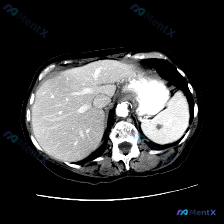

整理了一份很有意思的读片病例,差点被最初的提问带偏,分享一下思路: 病例背景 核心提问是“这张图里脾脏有什么病变?”,先来看影像的客观描述。 关键影像信息(增强CT横断面) 1. 扫描层面与质量:上腹部增强,对比度好,结构清。 2. 我们重点看的脾脏:边缘轮廓大致正常,未见明确局灶性低密度、高强化或...

今天看到一份很有意思的腹部CT读片案例,整理一下思路和大家分享。 病例背景 用户最初的问题是「识别图中的脾脏病变」,但拿到图像(腹部CT横断面软组织窗)后,先按流程做了系统评估。 --- 影像关键信息整理 先把看到的客观情况列出来: 1. 脾脏:形态大小正常,包膜光滑,密度均匀,未见任何局灶性异常,...

最近看到一个读片资料,预设问题是“图像中是否存在脾脏病变”,先和大家理一下完整的思路。 --- 先列一下拿到的「影像客观事实」 这是一幅上腹部CT软组织窗横断面图像: 1. 肝脏:轮廓平整,实质密度均匀,肝内血管走行清晰,无受压移位; 2. 脾脏:划重点——形态正常、大小正常、实质密度均匀,未见局灶...